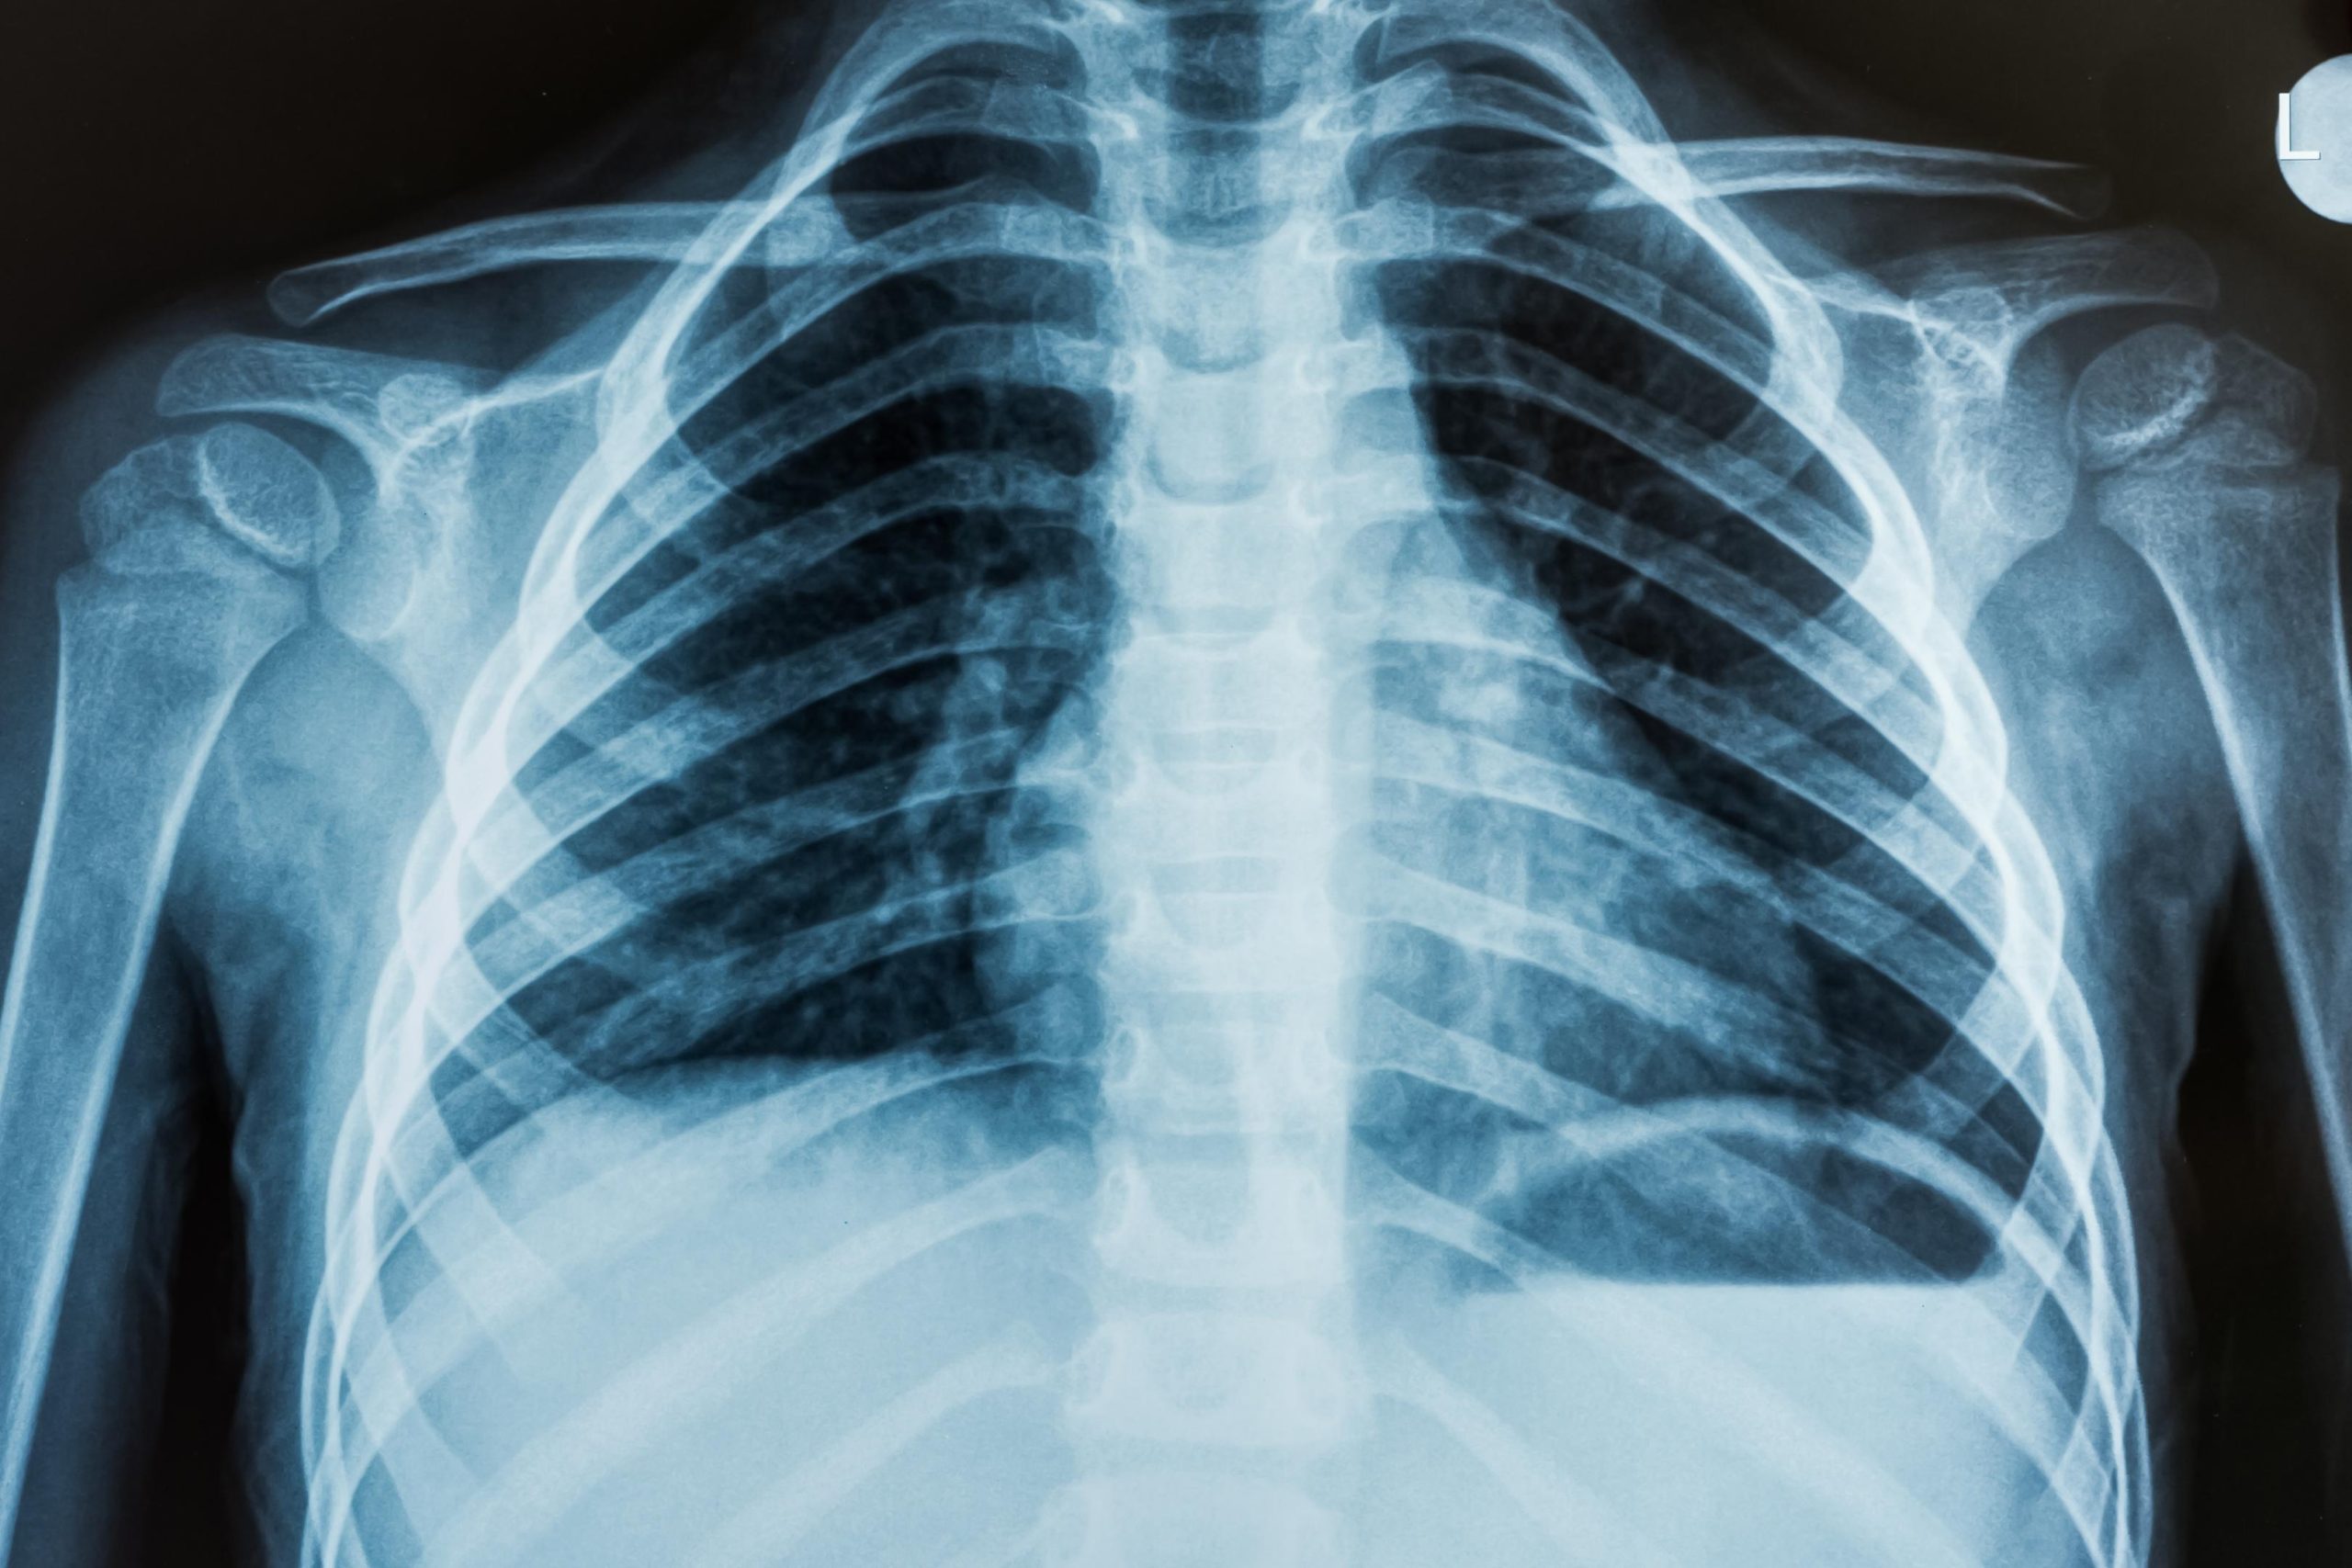

X-Rays